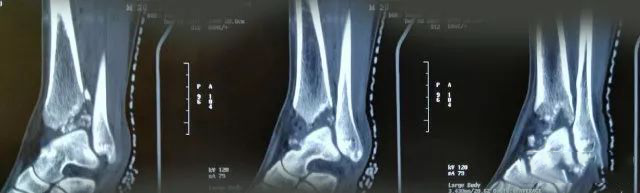

一起来看一个病例:男,20岁,摔倒右踝3天,体格检查示右小腿下段肿胀压痛,活动受限,运动感觉可,诊断为右侧 Pilon骨折。X片及CT三维图如下,欢迎投票并在评论区附上理由。